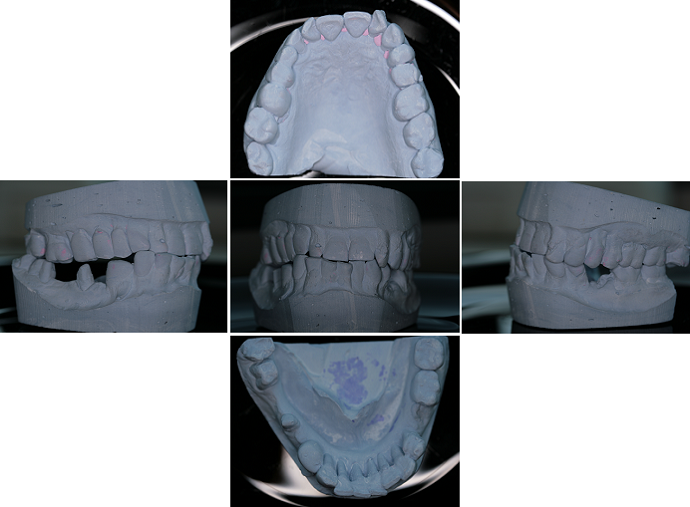

3) fotodokumentace - fotografie stavu chrupu a otisky na studijní modely

Fotodokumentace a model se provádí u pacientů s potřebou kompletní rekonstrukce chrupu.

Foto 9-13: Fotodokumentace situace v ústech - vlevo, vpravo, uprostřed, v horní a dolní čelisti.

Fota 16-20: Fotografie modelu vytvořeného na základě otisků.

V tomto případě je pro lékaře obzvláště důležité provést podrobné vstupní vyšetření včetně fotodokumentace, protože tvorba terapeutického plánu probíhá za nepřítomnosti pacienta. Na základě rozboru fotografií, skusových poměrů na studijních modelech a srovnání poznatků z rentgenologického vyšetření s vlastní prohlídkou dutiny ústní jsou navrženy možné postupy ošetření s cenovým návrhem. Vše se odesílá pacientovi emailem k odsouhlasení, případně je pozván ještě na jednu konzultaci, kde se mu možné postupy vysvětlí a dohodne se, jaké řešení je ochoten akceptovat. Akceptací je myšleno např. rozhodnutí se mezi fixním a snímatelným řešením (např. implantáty versus protéza), někteří klienti nechtějí podstoupit časově náročnou léčbu zubu, u kterého nelze stanovit dobu přežití na 10 let a více, tak se i přes možnost jeho záchrany rozhodnou pro pohodlnější řešení a to zub vytrhnout a nahradit ho dentálním implantátem (jednodušší řešení se stejnou životností).